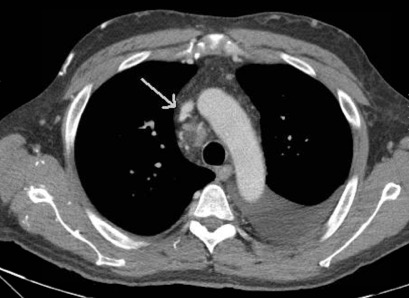

Figure 2. Axial chest CT demonstrating occlusive stenosis of the central portion of the innominate vein and SVC confluence.

Given his chronic immunosuppression, he was admitted by internal medicine for initiation of intravenous (IV) antibiotics. Thoracic surgery, transplant infectious disease, and nephrology were consulted following admission. He underwent an echocardiogram, which did not demonstrate congestive heart failure. A computed tomography (CT) scan demonstrated right internal jugular occlusion, superior vena cava (SVC) stenosis, prominent thoracic venous collaterals, and cervical and mediastinal lymphadenopathy (Figures 1 and 2). His pleural fluid cytology and cultures were negative, but testing indicated the presence of chylomicrons and his triglyceride level was 1154 mg/dL, which was consistent with a chylothorax.